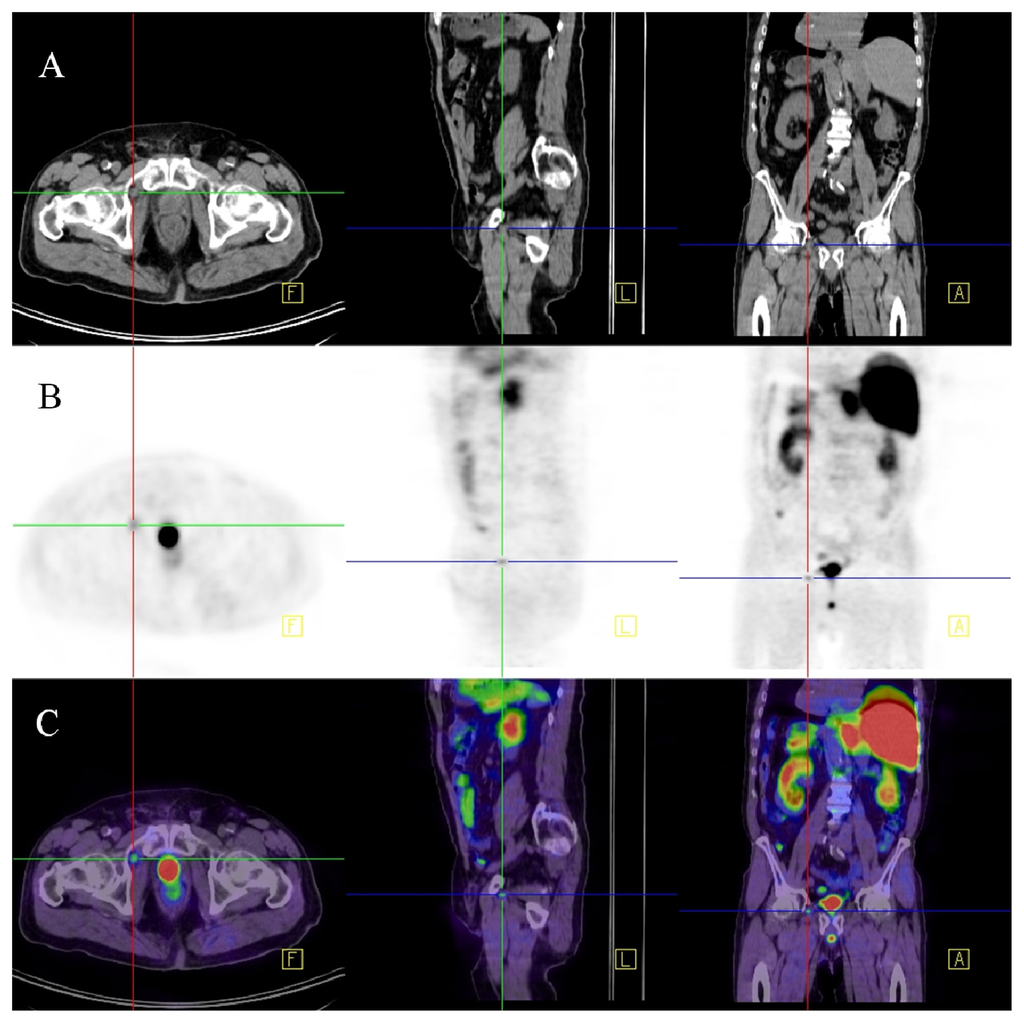

Figure 2.

68Ga-PSMA-PET-CT. Patient with prostate cancer (status after brachy-therapy and bilateral iliac lymph node dissection, current PSA 21 μg/L). PET images were acquired after the administration of 68GA-PSMA-Ligand (60 min thereafter). The figure shows fused images (PET-CT): On the coronal view (A) a pathologic isotope uptake in multiple lymph nodes in the right para-iliac region and infra-carinal (mediastinum) is clearly visible; the corresponding transversal images show the para-iliac (B) and infra-carinal (C) lymph nodes with elevated uptake of the tracer. The corresponding transversal native CT images present these suspect structures (D,E) as normal sized lymph nodes (marked by red arrows).